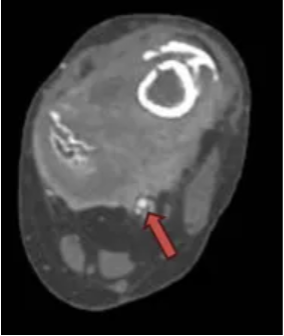

图示:箭头所示腘动脉

但麦麦提的妈妈于心不忍那么小的孩子就失去一条腿,几经辗转,最终通过校友联系到了上海市第一人民医院骨肿瘤科姜亚飞医生。经过全科讨论,决定采取股骨远端瘤段切除+膝关节肿瘤半关节定制假体置换的手术方式。